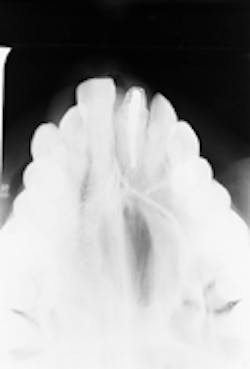

The patient`s most recent radiographs were taken approximately one year earlier; no lesion was evident on the previous radiographs. After a thorough clinical examination, a maxillary occlusal radiograph of the involved area was ordered. Examination of the occlusal radiograph revealed a large, well-defined radiolucency (see radiograph).